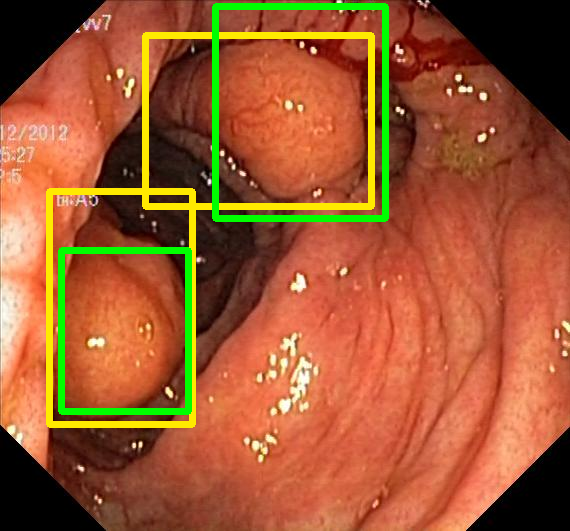

We evaluate the resulting object detection models using the test data, which is pre-processed in the same manner as the validation data, with AP@[.5:.95] (AP for conciseness), AP@.5 (AP50), and AP@.75 (AP75) computed for predicted bounded boxes with a confidence score \geq0.05. For all metrics, a higher value indicates better performance. The results are presented in Table VI, and some examples for predicted bounding boxes with a confidence score \geq0.5 are shown in Fig. 1.

Figure 1: Targets (yellow bounding boxes) and predictions (green bounding boxes) for two randomly selected instances of the Kvasir-SEG test set. For conciseness, we denote ResNet50s with RN, ViT-Bs with VT, Hyperkvasir-unlabelled with HK, ImageNet-1k with IN, MoCo v3 with MC, Barlow Twins with BT, MAE with MA, supervised pretraining with SL, and no pretraining with NA-NA.